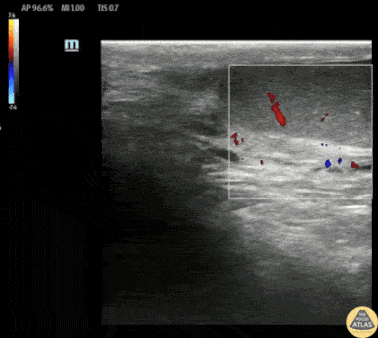

Teenaged male presented with acute onset unilateral testicular pain and swelling. On exam, the affected testicle was swollen and tender with some color change. POCUS demonstrated normal flow in a normal sized contralateral testicle, and an enlarged affected testicle with no color doppler flow. After manual detorsion, POCUS demonstrates clear restoration of normal blood flow. After urologic consultation, the patient was taken emergently to the OR, where operative findings confirmed testicular torsion, and orchiopexy was performed. Dr. Michael Duerson, PGY4 Denver Health Residency in Emergency Medicine